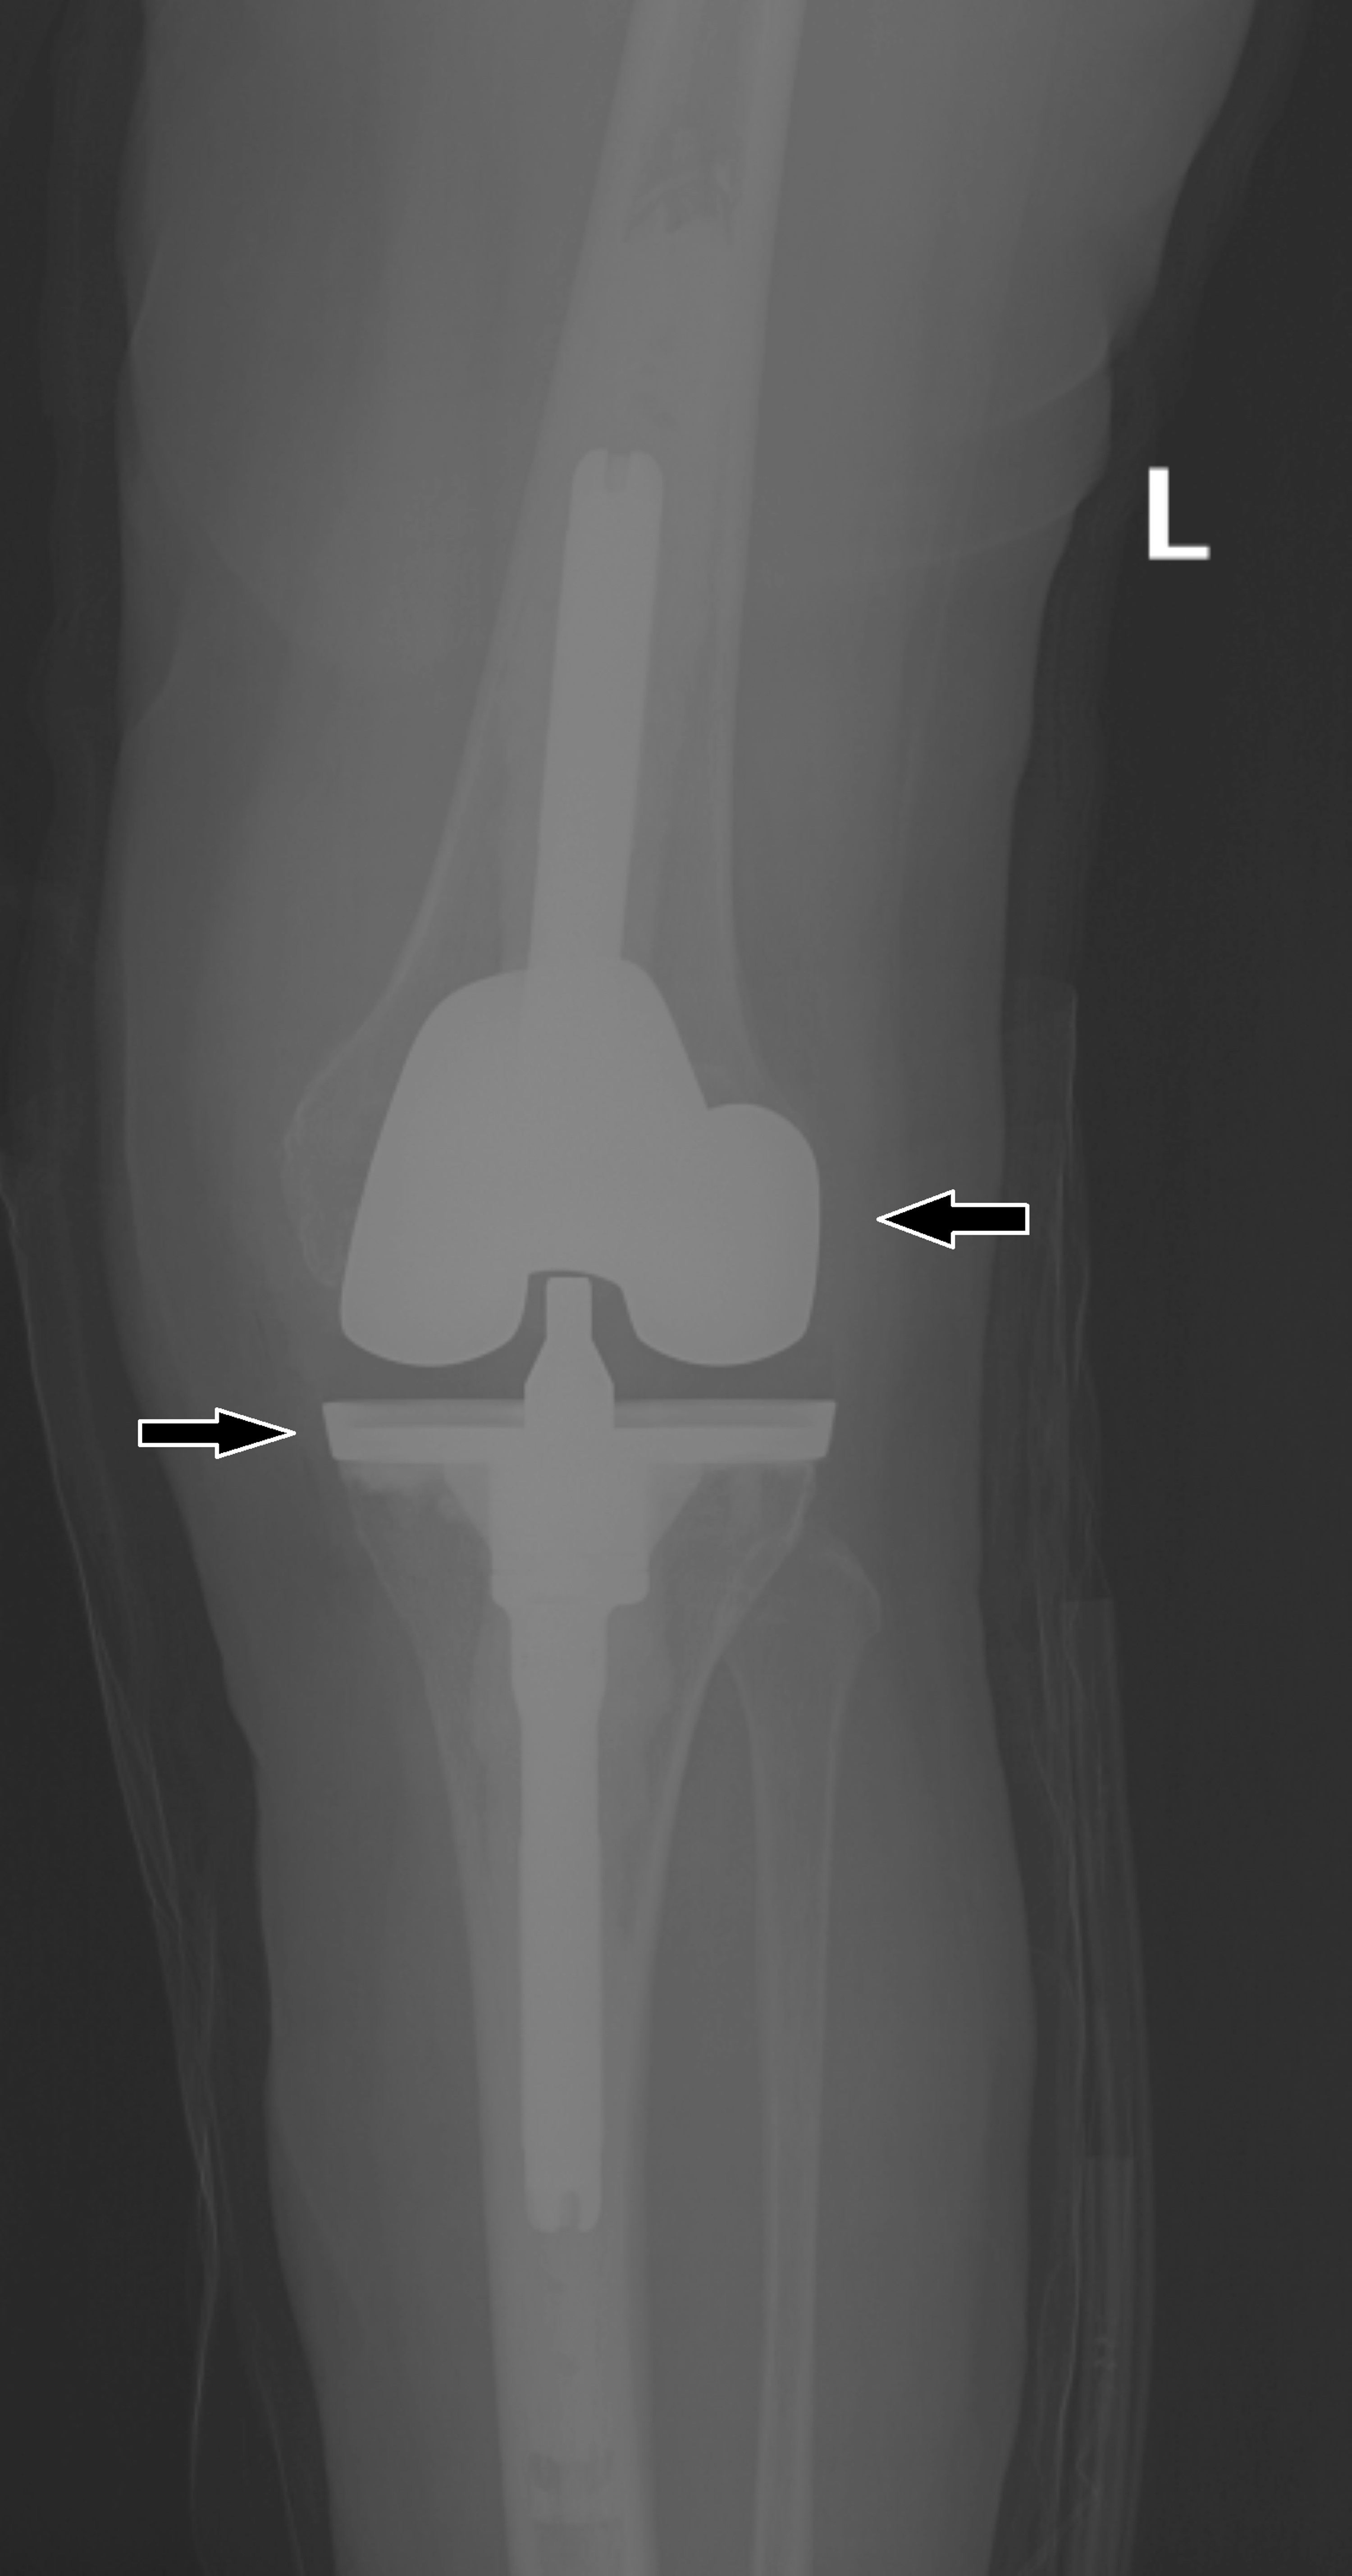

Figure 3 from TwoStage Revision Using a Modified Articulating Spacer Replacing Spacer Total Knee Replacement In this procedure, your doctor removes some or all of the. When a total knee replacement prosthesis fails, a second knee surgery is required. Replacing a spacer is a much less severe operation than having a total knee replacement. The most common and effective treatment is called revision total knee replacement (also known. If your knee replacement fails, your doctor. Replacing Spacer Total Knee Replacement.